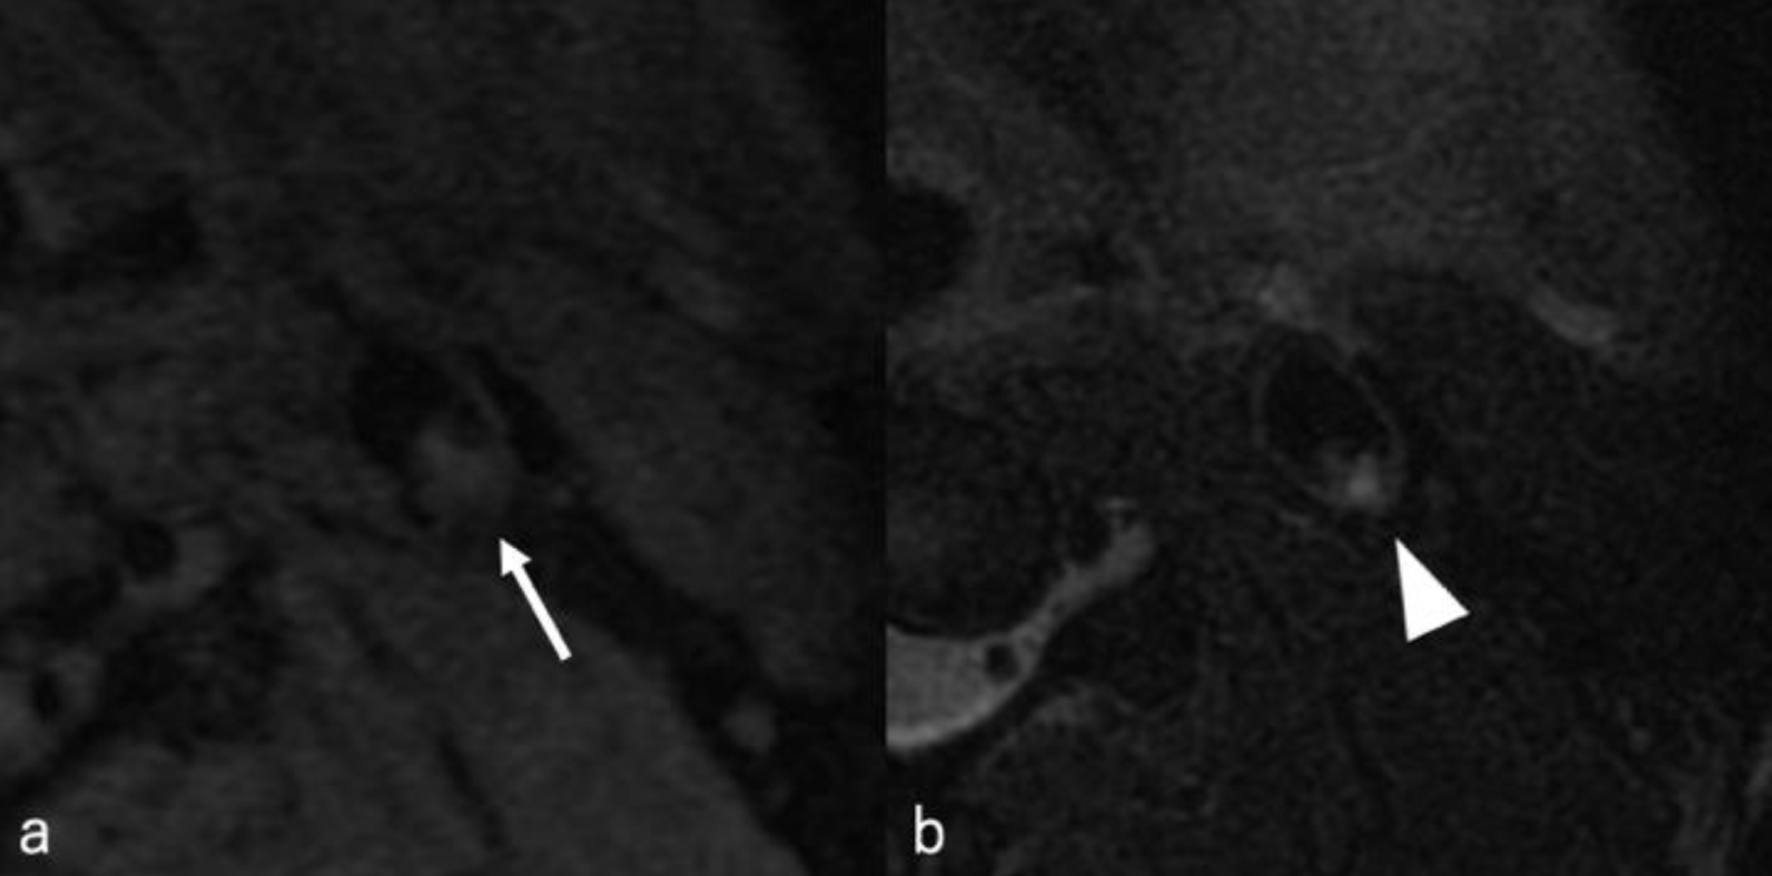

The following day, no apparent hemorrhagic extension was observed. On carotid artery ultrasonography, there was a mobile lesion at the origin of the left ICA (Fig. 2). Further examination with three-dimensional computed tomography angiography (3D-CTA) revealed the presence of irregular contrast in the posterolateral wall of the left cervical ICA origin (Fig. 3a-d). MRI plaque image revealed a structure that was T1 isointense (Fig. 4a) and T2 high intense (Fig. 4b) with the vessel wall, protruding into the lumen (Fig. 4). On the second day, cerebral angiography revealed a shelf-like structure on the posterior wall of the left ICA origin (Fig. 5a), and the left MCA was recanalized. Cerebral angiography revealed pooling of blood flow on the rostral side of the lesion (Fig. 5b).

Figure 4. MRI plaque image revealed a structure that was T1 isointense (white arrow) (a) and T2 hyperintense (white arrowhead) (b) with the vessel wall, protruding into the lumen. MRI: magnetic resonance imaging.

CW has a relatively low detection rate on carotid artery echocardiography. Joux et al [8] noted that in 18 of 21 cases, CW was not obvious and could be misdiagnosed as fibrous plaques since the findings were nonspecific. Thomas et al [9] demonstrated the superiority of cerebral angiography and CTA compared with carotid artery echocardiography in the diagnosis of CW. In the present case, we were able to identify a thrombus that seems to be attached to the lesion, but the lesion itself could not be observed. On MRI plaque image, the structure of CW typically has a continuous signal with the vessel wall that protrudes into the lumen from the posterior wall of the origin of the ICA [6, 11]. The same MRI findings were observed for this patient. Reportedly, the CW intensity on MRI plaque imaging typically appears as T1 isointense and T2 hyperintense signals [12, 13]. Herein, the areas identified as CW showed T1 isointensity and T2 hyperintensity, consistent with previous findings. In contrast, the areas identified as attached thrombus demonstrated T1 isointensity and T2 hypointensity. Kimura et al [12] presented a case wherein an attached thrombus disappeared over time; the thrombus showed T1 and T2 isointensity, whereas the CW region revealed T1 isointensity and T2 hyperintensity. Although the signal intensity of the thrombus in our case slightly differs from that report, the CW intensity pattern remains consistent. Furthermore, MRI in our case revealed a hemorrhagic infarction in the left MCA region. The mechanism underlying the hemorrhagic infarction may include the presence of a thrombus in the proximal M1 segment, potentially including the perforating arteries. As the thrombus migrated distally along the M1, transient reperfusion of the perforators may have led to hemorrhagic changes.